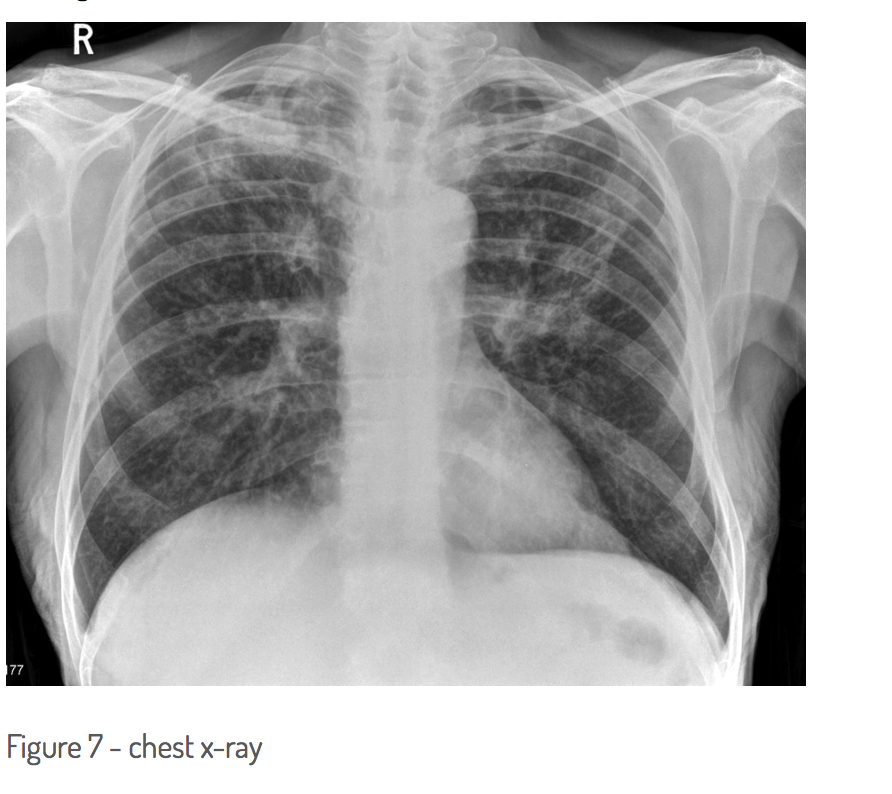

CXR should be performed to demonstrate previous/active pulmonary TB (half of patients dont present with hx of pulmonary TB)

CXR - what are the findings?

most likely underlying diagnosis given the chest radiograph?

bilateral ill defined upper lobe infiltrates/consolidation

tuberculosis

no - TB more likely with CXR findings - treat TB after obtaining sputum sample